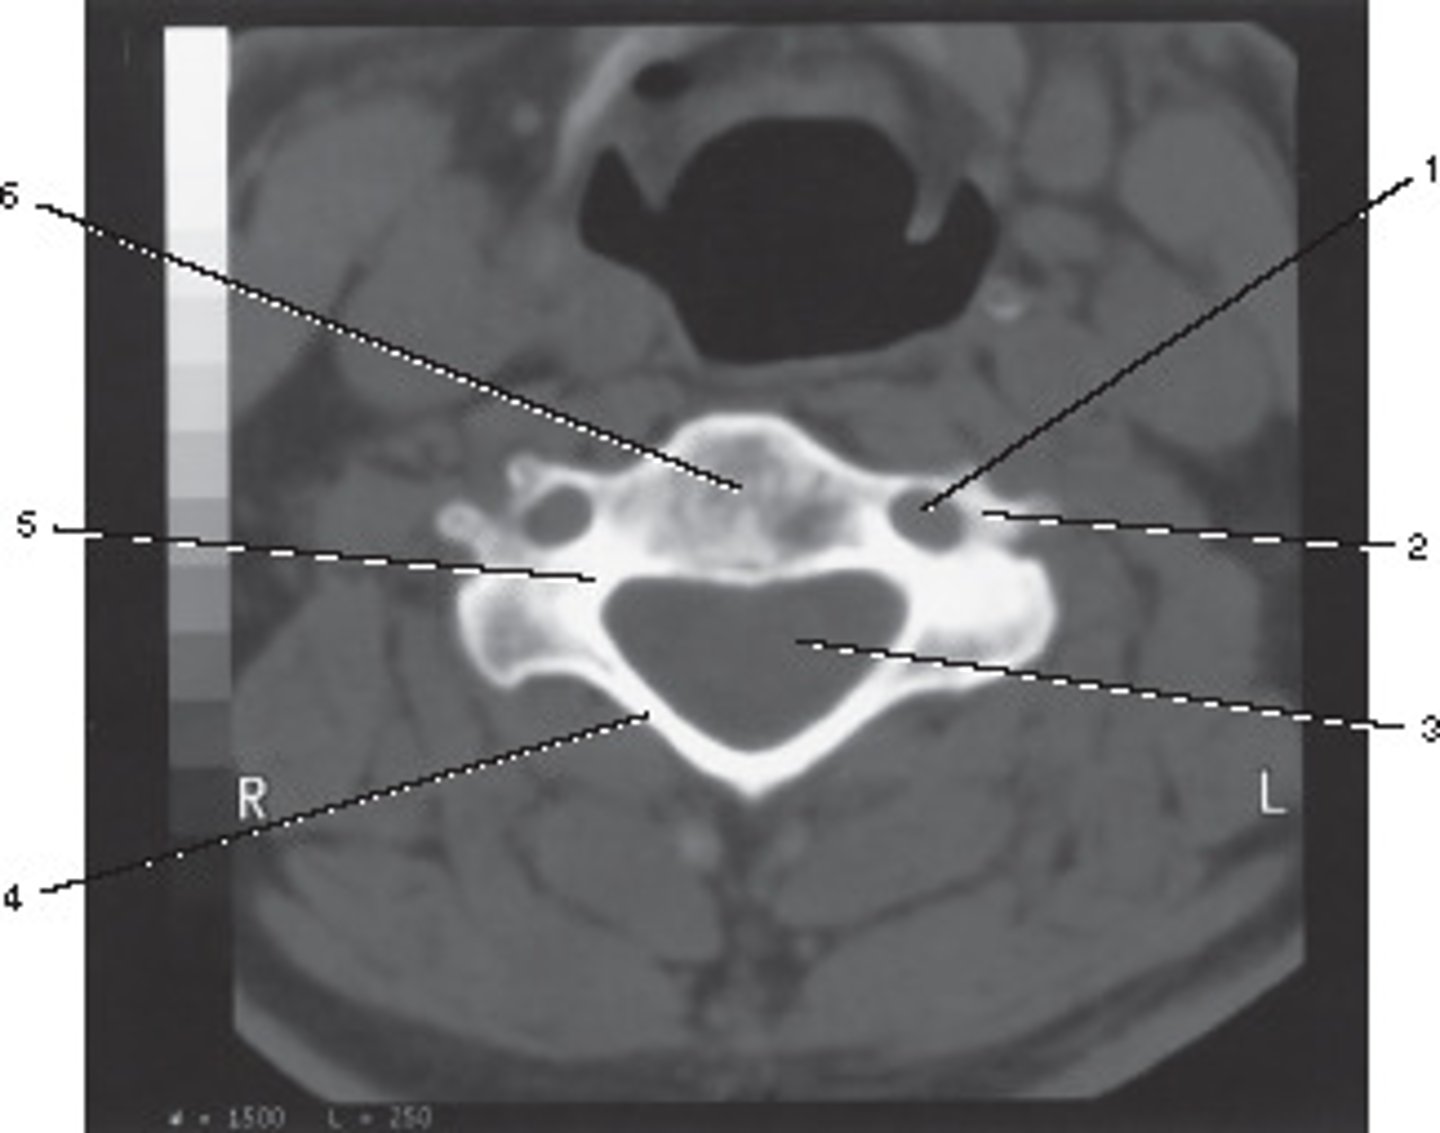

Body

Identify structure A on this axial CT slice of the lumbar vertebra.

<p>Identify structure A on this axial CT slice of the lumbar vertebra.</p>

Pedicle

Identify structure B on this axial CT slice of the lumbar vertebra.

<p>Identify structure B on this axial CT slice of the lumbar vertebra.</p>

Lamina

Identify structure C on this axial CT slice of the lumbar vertebra.

<p>Identify structure C on this axial CT slice of the lumbar vertebra.</p>

Transverse process

Identify structure D on this axial CT slice of the lumbar vertebra.

<p>Identify structure D on this axial CT slice of the lumbar vertebra.</p>

Posterior spinous process

Identify structure E on this axial CT slice of the lumbar vertebra.

<p>Identify structure E on this axial CT slice of the lumbar vertebra.</p>

Vertebral foramen

Identify structure F on this axial CT slice of the lumbar vertebra.

<p>Identify structure F on this axial CT slice of the lumbar vertebra.</p>